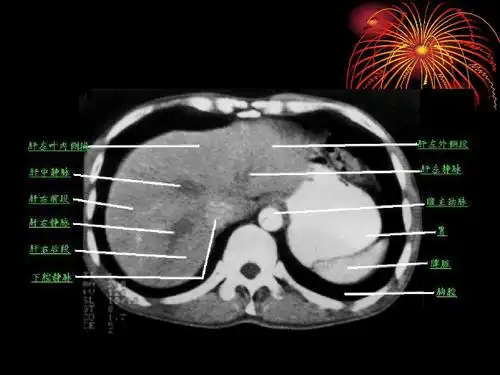

胰腺癌,炎ct诊断ppt